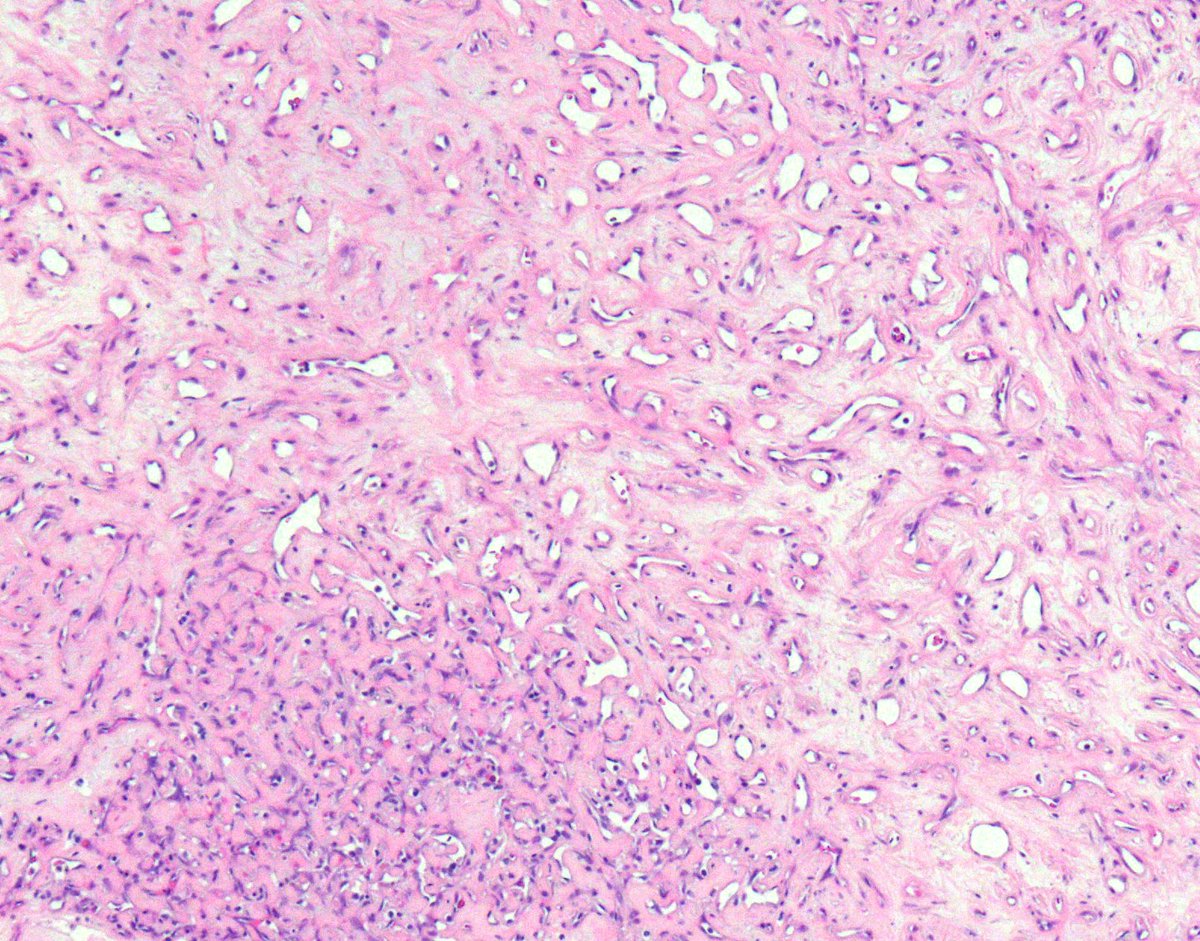

4.3 cm renal mass confined to kidney, tumor cells are predominantly with proliferative, tubular pattern 🎨 CK7 positive (strong, diffuse) 🎨 CD117 negative Thoughts? Sean R Williamson MD Kiril_T_Can Michelle_Hirsch (Donovan) Priya Rao, MD Ankur Sangoi

Kidney, young F adult #gupath Dr. Luca Olaleke Folaranmi Aurélien Morini, MD, MSc 🇫🇷🇪🇺💙💛 Celina Stayerman MD 🔻Nusrat Zahra🔻🇵🇸 @miss_me1986 Gonzalo De Toro Tristan Rutland MBBS FRCPA IFCAP Anandi Lobo, MD Sumanta Das Lorand Kis Erik Kouba bansar Carlos Miguel Ruiz Carlos Nieves Padma Priya J Susan Prendeville @AkgulMd Ankur Sangoi Barry McGinn